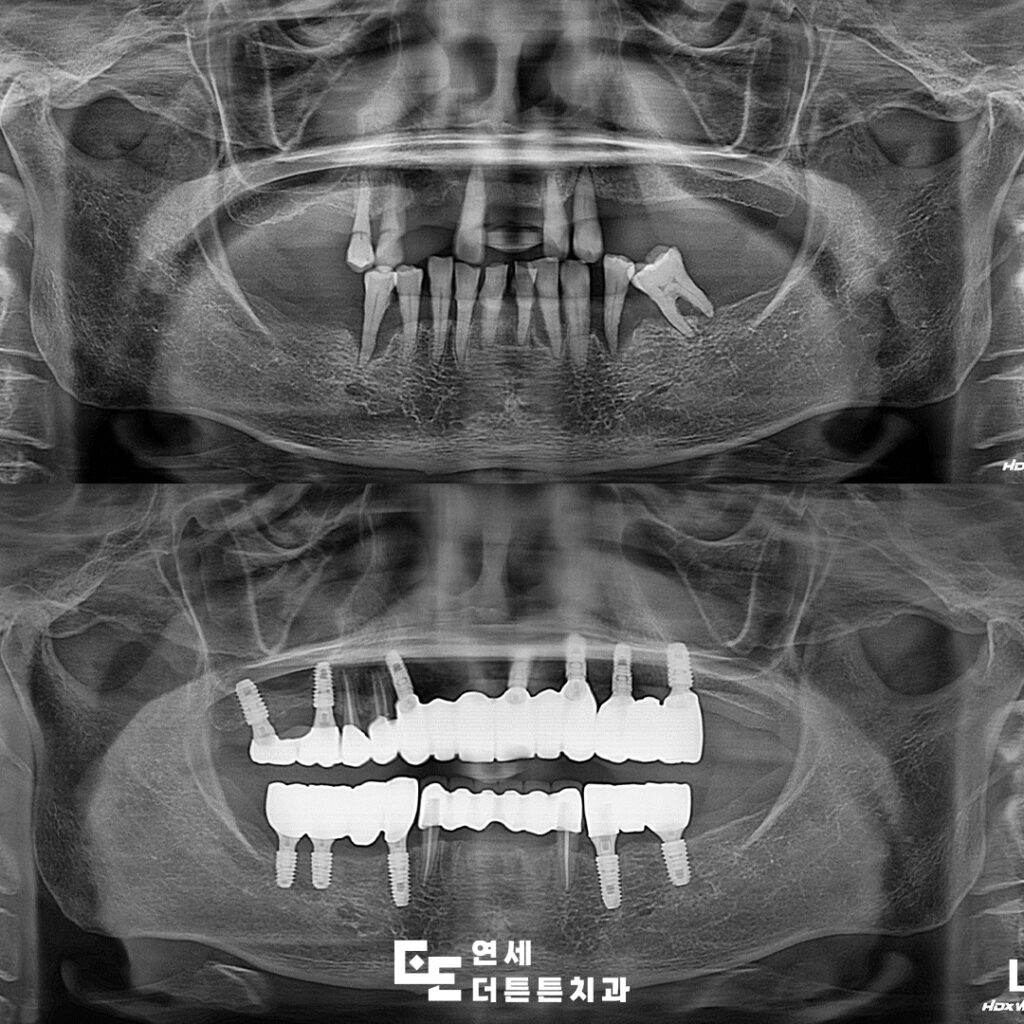

방학역치과 연세더튼튼치과에서 소개해 드릴 사례는

예후가 좋지 않은 자연치들을 발치한 이후

임플란트를 통해 구강 기능을 회복한 치료 과정입니다.

기능과 심미성을 함께 고려하여

최종 보철물 장착까지 마무리된 상태입니다.

방학역치과 사례와 같이 전체 임플란트를 계획할 때에는

부분 임플란트와 달리 식립 개수뿐 아니라

위치와 교합 관계까지 전체적인 균형을 고려한

치료 계획이 필요한데요.

특히 잇몸뼈의 흡수가 많이 진행된 경우에는

단순한 식립만으로는 충분한 안정성을

확보하기 어려울 수 있어

상악동 거상술이나 치조골 이식과 같은

추가적인 처치가 함께 이루어지기도 합니다.

이러한 과정을 통해 임플란트가

안정적으로 자리 잡을 수 있는 환경을 마련하고

장기적인 사용을 위한 기반을 확보하게 됩니다.